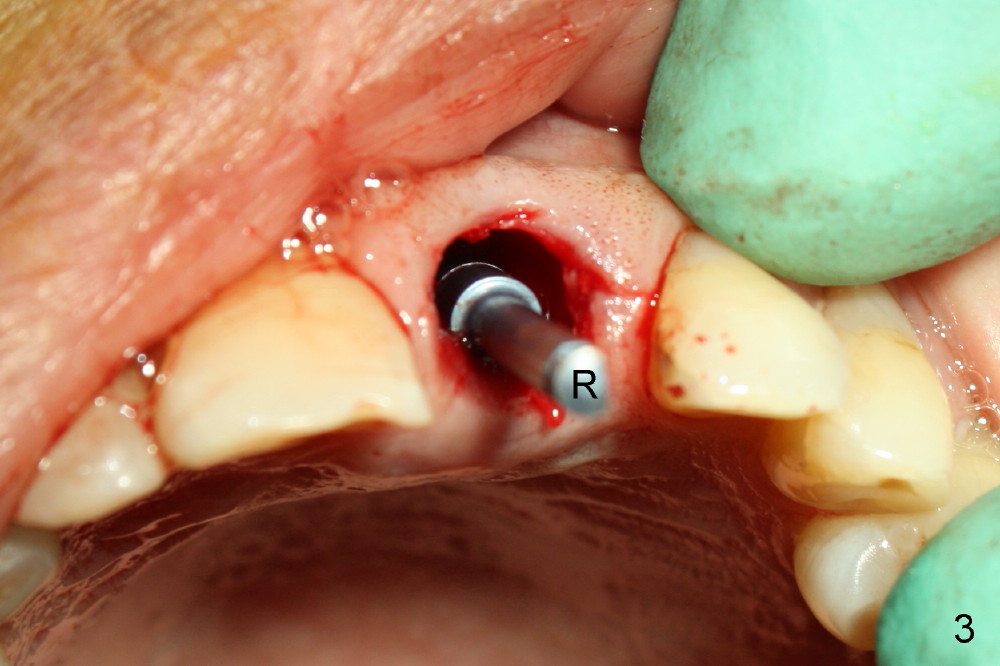

After extraction, osteotomy is made as palatally as possible so that the end of a reamer/drill (Fig.3 R) in the line of the incisal edge of the neighboring teeth. The depth of the 3.5 mm reamer is 14 mm from the crest (Fig.4 <). Next, a 5x17 mm tapered implant is placed with insertion torque > 60 Ncm (Fig.6). A 4 mm 0° unipost is permanently cemented (Fig.5: P). Finally a provisional is cemented on a temporary basis (Fig.7,8: T). There is no contact in centric or any lateral excursions.